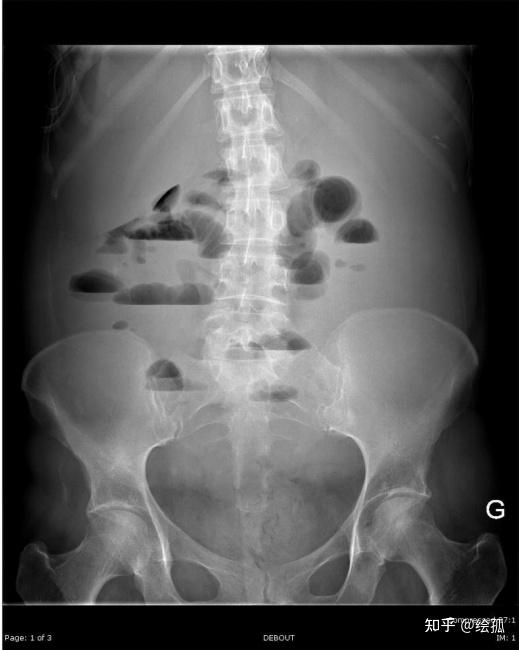

肠梗阻液平面图片

肠梗阻 检查部位:腹部立位, 检查所贝: 腹部示有多个大小不等的气液平

肠梗阻x线影像揭秘:快速识别.@li志强医生的动态

肠梗阻 #手术 #立位腹平片 #急诊 可以看到多发的气液平面

梗阻段以上空肠,回肠内可见多发长短不一,阶梯样气液平面,管腔扩张